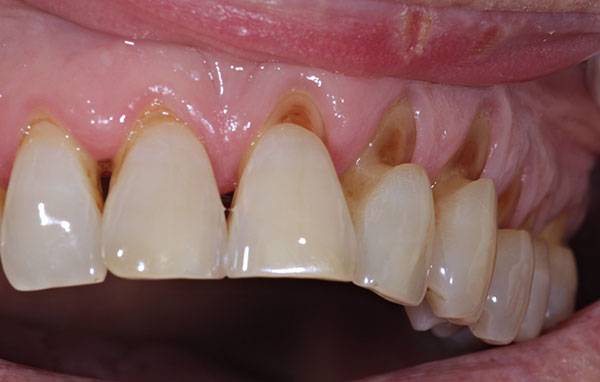

Many a times, you would have seen such notches in your teeth or in the mouth of some elderly person. Such notches create very unpleasant smile as food gets trapped in these notches and is seen while speaking or smiling.

These notches are called abrasion cavities. These cavities are not due to the germs but develop because of mechanical insult to the tooth. These are predominantly because of improper brushing style or using hard tooth brush. These cavities start as small notches which may or may not be accompanied with sensitivity.

The worst thing about such cavities is that they develop in multiple teeth at the same time. Sometimes, it involves almost all teeth. Getting such cavities filled with tooth coloured fillings is a preventive therapy you would want to give yourself or your loved ones to save on the treatment time as well as the associated cost.